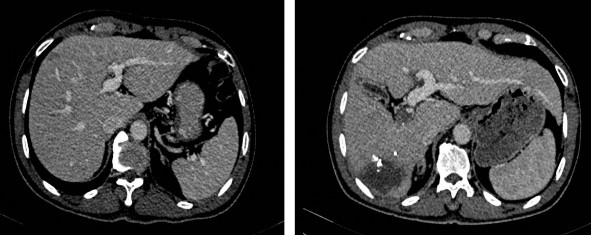

Khi thể tích gan bảo tồn không đủ để cắt gan lớn, các bệnh nhân sẽ được thực hiện phì đại gan bằng thủ thuật thuyên tắc tĩnh mạch cửa hoặc phẫu thuật ALPPS thì một. Sau đó, thể tích gan bảo tồn sẽ được đo lại trước khi quyết định phẫu thuật cắt gan.

Hình 2.4. Gan trái trước (24/03/2020) và sau PVE (09/04/2020) (BN A08-0021732)